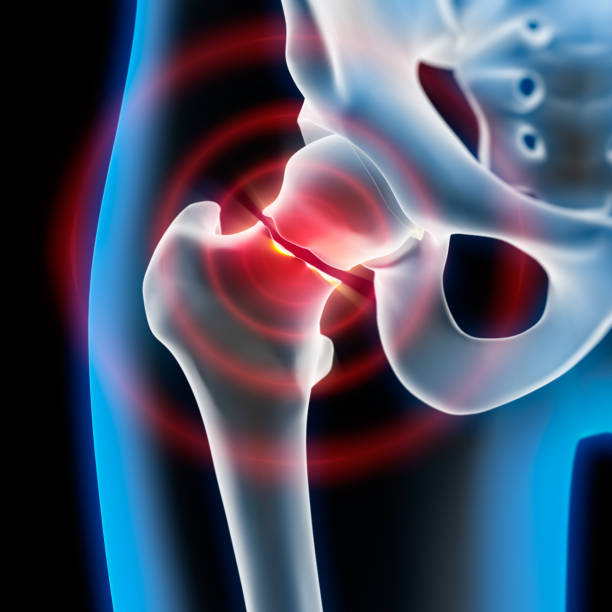

골반 통증 원인 7. 퇴행성 고관절염

골반 통증 원인 일곱 번째는 퇴행성 고관절염입니다. 퇴행성 고관절염은 고관절 부위 연골이 마모되고 손상되는 증상을 말하는데 별다른 외상이 원인이 아니라 퇴행성 변화로 인하여 이러한 통증을 유발하게 됩니다. 이 증상으로 말미암아 관절운동 범위가 축소되는데 동시에 절뚝거리는 증상을 동반하며 골반 통증이 생깁니다.